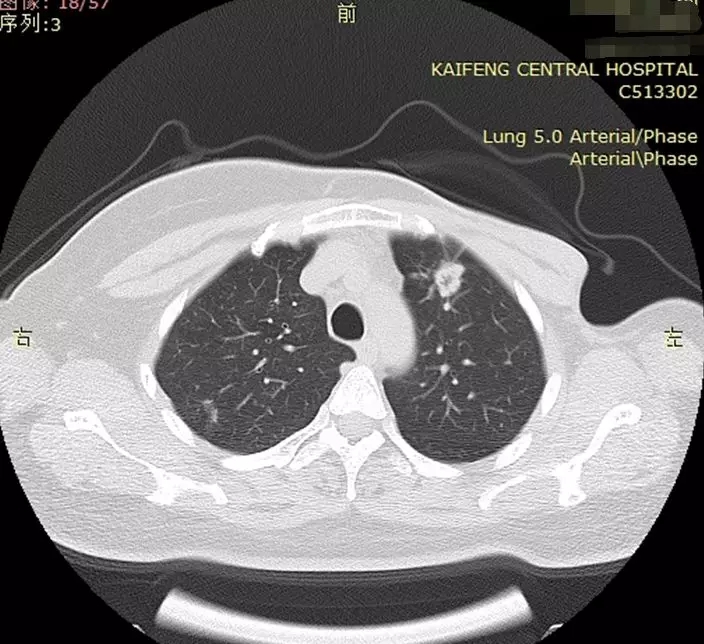

小马的爱人黄某某,37岁,2年前体检发现乳腺癌,年纪轻轻的她一下子打蒙了,整天在家以泪洗面,小马知道这个消息更是晴天霹雳,孩子还那么小,爱人就得了恶性肿瘤,往后的日子怎么过,最后是在我院乳腺外科手术治疗,术后做过几次化疗,中间一直观察,病情一直稳定,可是这次检查发现左上肺叶有一个肿瘤形成,本来刚刚有点起色的家庭被这次检查再一次打蒙了。穿刺病理证实为肺腺癌肺癌,为肺部原发性癌,与上次乳腺癌无关联。再次来到医院,面对这个结果小马彻底失望了,第一次的手术和化疗让原本美丽的妻子已经很憔悴了,还要再来一次吗?手术创伤多大,病人能不能耐受?这些问题让他痛苦不堪。

术前CT

于是他就找到了我,看过病人的CT片子,肿瘤不大,全身检查没有发现转移,能做微创胸腔镜手术,我说完小马明显松了一口气,又问:确定能做微创吗?我肯定的说“能!”小马的表情一下子就灿烂起来了,激动地说:“主任,您有信心,我就有信心!”看到这一幕,我的心情沉甸甸的,感到自己肩上的责任重大,对于我们医生来说,她就是一个患者,我们每天的工作就是手术,可是对于病人家庭来说,她是一个妻子,一个母亲,一个女儿,失去她就是失去了天。